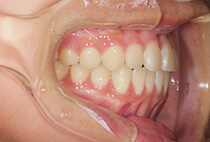

治療前

治療後

しっかり前歯を下げるために、インプラントアンカーを使用してコントロールしました。

かみ合わせが整うと咬筋の過緊張が改善。

過緊張による筋肉肥大も改善しフェイスラインもすっきりしました。